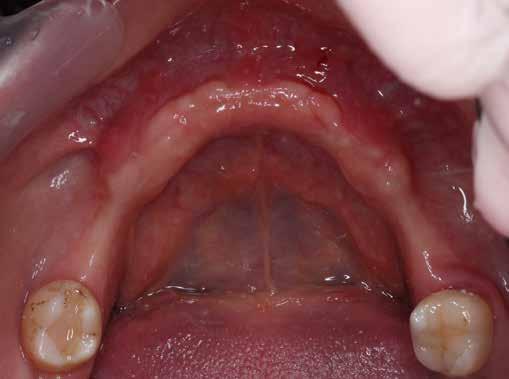

Az 50 éves nőpáciens az alsó és felső állcsont területén egyaránt panaszt (fájdalom, ráharapási érzékenység) okozó, harmadfokban mozgatható fogak miatt jelentkezett rendelőnkben. Az általános anamnézisben említést érdemlő betegség, műtét nem szerepelt. Az elvégzett klinikai és radiológiai vizsgálatok (1–2. ábra) alapján fogai reménytelen parodontális státusúnak bizonyultak, hosszú távon sem megtartásuk, sem protetikai célú felhasználásuk nem volt lehetséges. A parodontális prognózis a fogak eltávolításának abszolút indikációját jelentette. Ezáltal mindkét állcsontban teljes foghiány kialakulásával kellett számolnunk. A protetikai szemléletű, „visszafelé” tervezés elveit követtük a hosszú távú funkcionális, esztétikai siker és szöveti stabilitás elérése érdekében: mindkét állcsontban overdenture típusú fogpótlás készítése mellett döntöttünk. A megfelelő implant-protetikai rehabilitáció alapja az implantátumok megfelelő pozicionálása. A korábbi parodontális kórfolyamat következtében a processus alveolarisokat érintő eredendő csontdeficittel kellett számolnunk, amelyet tovább súlyosbíthatott volna a hagyományos extrakciós technikát követő involúciós atrófia. Ezért a páciens kivizsgálása és megfelelő előkészítése után a fog eltávolításával egy időben PRF

1. 3. 5. 8. 2. 4. 6. 7.